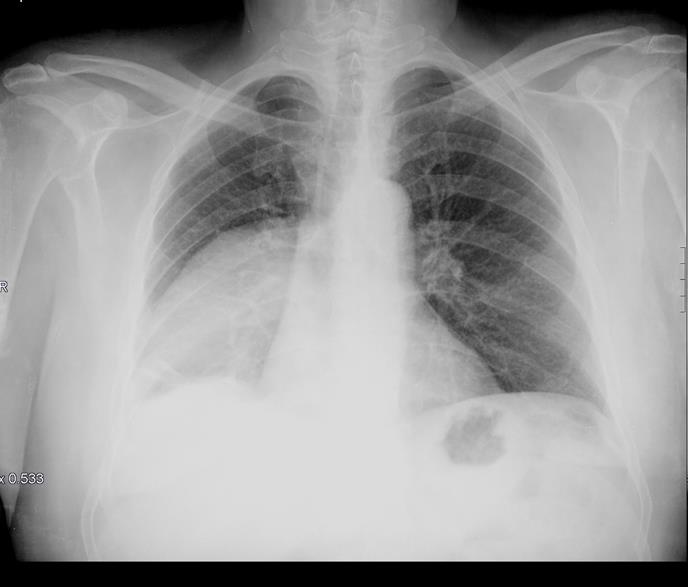

La Rx PA de tórax está indicada como técnica de primera elección en el estudio del aparato respiratorio, vía aérea y parénquima pulmonar, ya que aporta una visión general de forma rápida y precisa del estado cardiorrespiratorio del paciente. La proyección lateral, por su parte, es útil para valorar las zonas situadas detrás del corazón y las áreas paravertebrales y posterobasales. Es una técnica accesible y sencilla, que no precisa preparación previa.